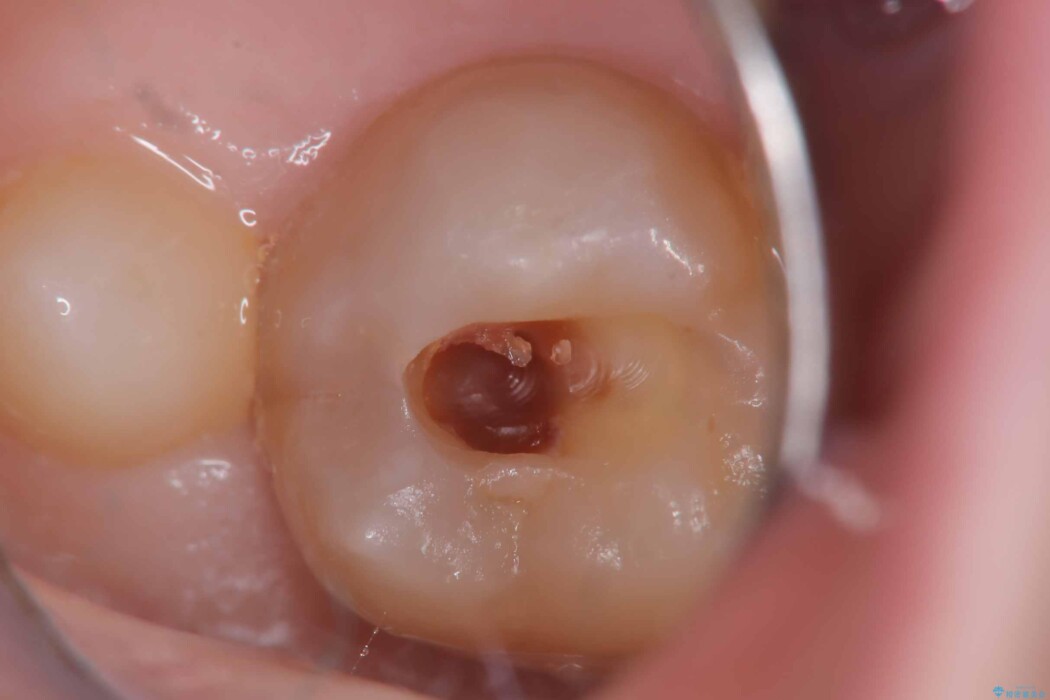

まずは古い詰め物と虫歯を丁寧に除去します。

除去後は、再発リスクを抑え長期的な安定を図るために、適合精度が高く劣化しにくいセラミックインレーによる修復を計画しました。